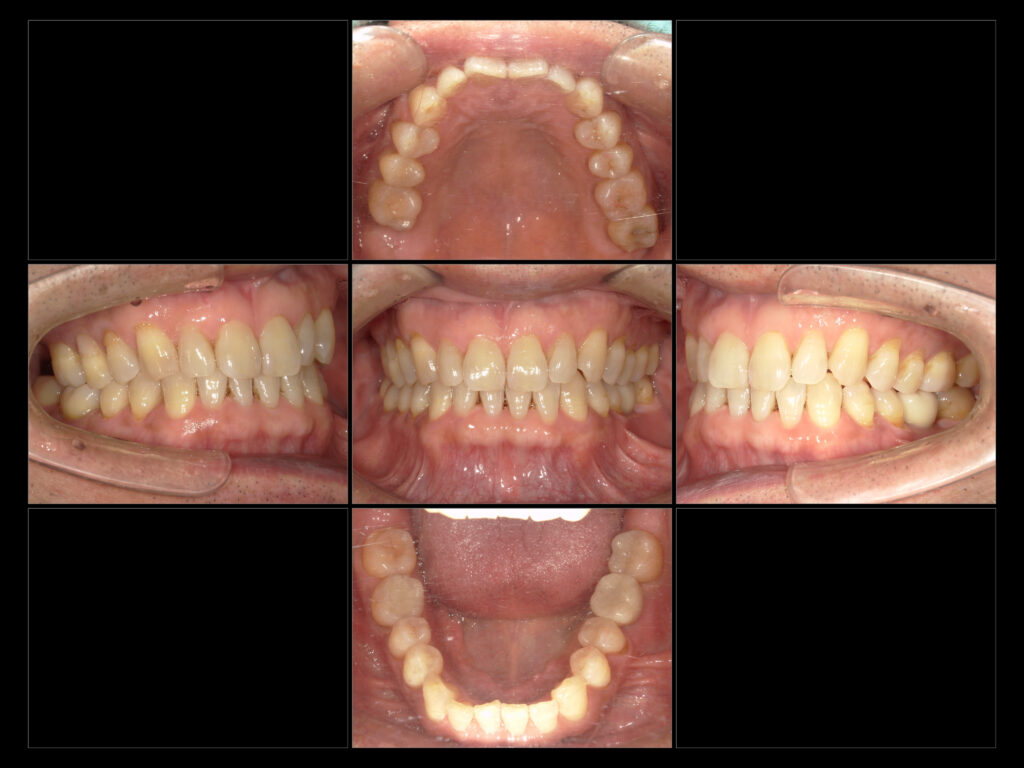

R8 2/17 治療終了時口腔内写真

●治療内容 左下6インプラント

左下57右下6 e-maxIn

●治療期間 1年2ヶ月 現在メインテナンスで経過観察中

●費用 764,500円